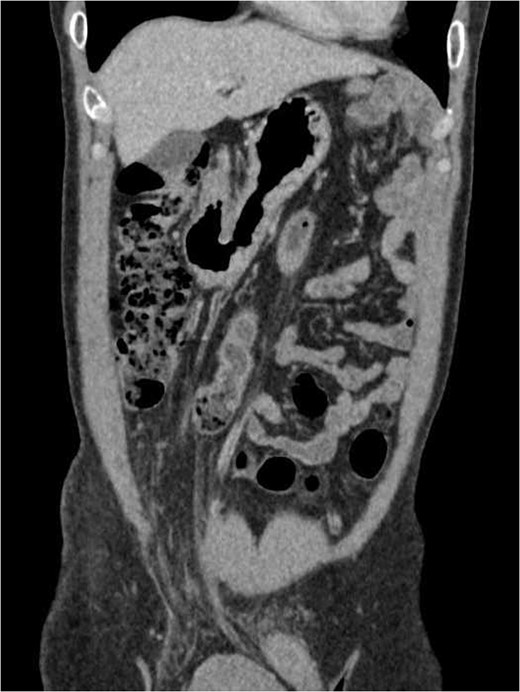

We proceeded with an ultra-sonographic examination of the scrotum, which revealed a heterogeneous mass within the right scrotal sac measuring 7.0 cm × 6.2 cm. The normal right testicle was not seen (Fig. 1). The features were pointing towards a right testicular tumour. Thus, a computed tomographic (CT) scan was ordered, which revealed a right inguinal hernia containing greater omentum and a heterogeneous mass suggestive of a right testicular tumour as seen on the ultrasonography (Figs 2 and 3).

Cross-sectional view of the lower abdomen CT scan revealed a right inguinal hernia containing the greater omentum and a heterogeneous mass.